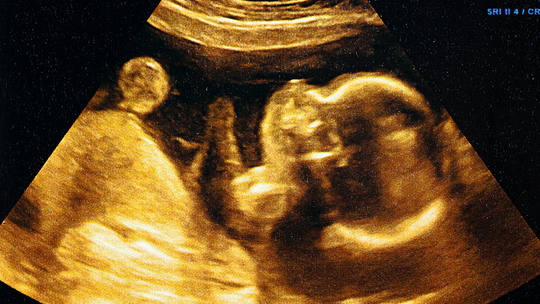

"Common Causes of Miscarriage in Early Pregnancy: What You Should Know\",\"imageid\":\"131009054\",\"imgsize\":\"1661384\",\"lu\":\"May 12, 2026, 02:25 PM\",\"id\":131009054,\"dl\":\"May 11, 2026, 03:00 PM\",\"seolocation\":\"pregnancy/causes-of-miscarriage-in-early-pregnancy\",\"subsecname\":\"Pregnancy\",\"subsecmsid\":112886004,\"syn\":\"It is very natural to experience happiness and a little anxiety simultaneously during the early weeks of pregnancy. Concerns about miscarriage are common, and many causes are not within your control. Learning about these can help you feel more supported.\",\"agency\":{\"id\":87654322},\"tn\":\"news\",\"imgratio\":\"0.5625\",\"dm\":\"t\",\"subsecseolocation\":\"pregnancy\",\"host\":\"prega\",\"slot\":\"10\"},{\"hl\":\"How Often Should You Bathe a Newborn Baby?\",\"imageid\":\"131005010\",\"imgsize\":\"35408\",\"lu\":\"May 11, 2026, 01:00 PM\",\"id\":131005010,\"dl\":\"May 11, 2026, 01:00 PM\",\"seolocation\":\"baby/bathing-newborn-baby-how-often-should-you-do-it\",\"subsecname\":\"Baby\",\"subsecmsid\":113631885,\"syn\":\"Bathing your newborn can feel both special and a little overwhelming, especially if you are unsure how often to bathe them. Fortunately, newborns do not require everyday bathing. You can take care of your baby's sensitive skin, make bathing time a peaceful experience, and create a bonding experience by knowing the proper frequency and using safe, gentle bathing techniques.\",\"agency\":{\"id\":87654322},\"tn\":\"news\",\"imgratio\":\"0.5625\",\"dm\":\"t\",\"subsecseolocation\":\"baby\",\"host\":\"prega\",\"slot\":\"11\"},{\"hl\":\"Blood Clots During Pregnancy: Understanding the Risks and Complications\",\"imageid\":\"131002969\",\"imgsize\":\"1495735\",\"lu\":\"May 11, 2026, 11:00 AM\",\"id\":131002969,\"dl\":\"May 11, 2026, 11:00 AM\",\"seolocation\":\"pregnancy/blood-clots-during-pregnancy-risks-symptoms-prevention\",\"subsecname\":\"Pregnancy\",\"subsecmsid\":112886004,\"syn\":\"Blood clots during pregnancy are a serious matter, but the positive part is that they are uncommon and usually preventable with proper awareness and care. Many expectant parents worry about this issue because pregnancy naturally changes how the blood behaves. But understanding the facts helps you stay safe and enjoy this special time.\",\"agency\":{\"id\":87654322},\"tn\":\"news\",\"imgratio\":\"0.5625\",\"dm\":\"t\",\"subsecseolocation\":\"pregnancy\",\"host\":\"prega\",\"slot\":\"12\"},{\"hl\":\"IVF Complications: What Every Couple Should Prepare For\",\"imageid\":\"130957503\",\"imgsize\":\"1771006\",\"lu\":\"May 11, 2026, 09:00 AM\",\"id\":130957503,\"dl\":\"May 11, 2026, 09:00 AM\",\"seolocation\":\"getting-pregnant/ivf-complications-symptoms-and-risks\",\"subsecname\":\"Getting Pregnant\",\"subsecmsid\":112886008,\"syn\":\"In vitro fertilisation (IVF) offers real hope to many couples facing infertility challenges. While the procedure has become much safer over the years, it still carries certain risks and possible complications. Understanding these helps you prepare better and stay alert during the journey.\",\"agency\":{\"id\":87654322},\"tn\":\"news\",\"imgratio\":\"0.5625\",\"dm\":\"t\",\"subsecseolocation\":\"getting-pregnant\",\"host\":\"prega\",\"slot\":\"13\"},{\"hl\":\"Cervical Incompetence: The Silent Cause of Second Trimester Loss\",\"imageid\":\"130956971\",\"imgsize\":\"1233562\",\"lu\":\"May 08, 2026, 07:00 PM\",\"id\":130956971,\"dl\":\"May 08, 2026, 07:00 PM\",\"seolocation\":\"pregnancy/cervical-incompetence-second-trimester-loss\",\"subsecname\":\"Pregnancy\",\"subsecmsid\":112886004,\"syn\":\"For many women, this is their first encounter with a condition called cervical incompetence, and tragically, it often announces itself only after a loss. This walks you through what it is, why it happens silently, how it's diagnosed, and what treatments and monitoring options exist to protect your next pregnancy.\",\"agency\":{\"id\":87654322},\"tn\":\"news\",\"imgratio\":\"0.5625\",\"dm\":\"t\",\"subsecseolocation\":\"pregnancy\",\"host\":\"prega\",\"slot\":\"14\"},{\"hl\":\"Can You Plan a Pregnancy After Recovering From Cancer?\",\"imageid\":\"130956443\",\"imgsize\":\"1165295\",\"lu\":\"May 08, 2026, 05:00 PM\",\"id\":130956443,\"dl\":\"May 08, 2026, 05:00 PM\",\"seolocation\":\"getting-pregnant/pregnancy-planning-after-cancer-treatment\",\"subsecname\":\"Getting Pregnant\",\"subsecmsid\":112886008,\"syn\":\"Planning pregnancy after cancer recovery is possible for many individuals with proper medical guidance. Learn about fertility considerations, safe timing, and expert recommendations to help you make informed, confident decisions about stepping into parenthood.\",\"agency\":{\"id\":87654322},\"tn\":\"news\",\"imgratio\":\"0.5625\",\"dm\":\"t\",\"subsecseolocation\":\"getting-pregnant\",\"host\":\"prega\",\"slot\":\"15\"}]}]}]]\n"])